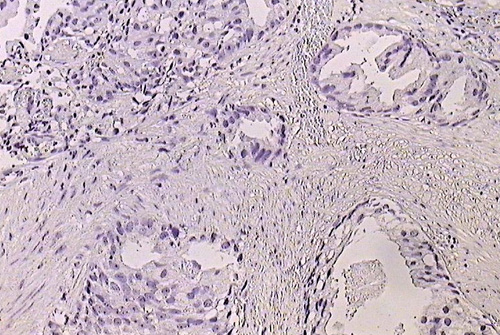

עם 1.3 מיליון מקרים חדשים בשנת 2018 ברחבי העולם, סרטן הערמונית נותר אתגר רפואי משמעותי. הטיפולים החדישים מתמקדים במסלול האנדרוגן בשל ההכרה בחשיבותם של אנדרוגנים במהלך של מחלת סרטן הערמונית העמידה בפני סירוס. על מנת להעריך את יעילות התרופות אבירטרון ואנזלוטמיד, קבוצת חוקרים ממספר מרכזים אונקולוגיים בניו יורק ניתחו נתונים מהמנהל האמריקאי לאזרחים ותיקים (VAMCs).

החוקרים מדווחים על שימוש בשיטה חדשה ללא תלות במרווחי הערכה ואידיאלית לניתוח בעולם האמיתי להערכת שיעורי צמיחת הגידול (g) ורגרסיה (d). תוך שימוש בתשתיות מידע אינפורמטיבי של VA ותמונות מחשוב, נאספו נתונים מ-5,116 אזרחים ותיקים עם סרטן ערמונית עמיד לסירוס שקבלו אבירטרון, אנזלוטמיד או שניהם.